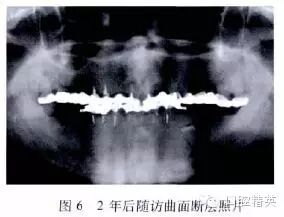

随访2年后,除下颌个别烤瓷牙出现局部崩瓷外(图5),未见其他牙髓和牙周问题,患者自觉效果良好。曲面断层照片显示(图6),患者剩余牙的根尖周无明显异常变化,牙槽骨未见明显吸收。